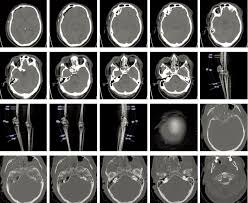

Was ist ein schädel hirn trauma. 2 Ätiologie Schädel-Hirn-Traumen entstehen durch Gewalteinwirkungen auf den Schädel und sind eine häufige Verletzung bei Stürzen und Unfällen. Das Schädel-Hirn-Trauma bezeichnet eine offene oder gedeckte Verletzung des Schädels und des Gehirns durch äußere Gewalteinflüsse. Wie gefährlich ist dieses und was ist es genau.

Ein Schädel-Hirn-Trauma kurz SHT ist eine Verletzung Trauma des Schädelknochens die mit einer Schädigung des Gehirns einhergeht. Egal ob ein unglückliches Ereignis beim Sport oder ein Autounfall schuld an einem Schädel-Hirn-Trauma kurz SHT ist die Verletzung trifft jeden unerwartet und verändert in schweren Fällen mit einem Schlag das komplette Leben. Das Schädel-Hirn-Trauma bezeichnet unterschiedlichste Kopfverletzungen die ihrerseits zu Verletzungen und Funktionsstörungen des Gehirns führen.

Unter einem Schädel-Hirn-Trauma versteht man Verletzungen des Schädels mit Beteiligung des Gehirns. Es führt zu Funktionseinschränkungen die sich je nach Schweregrad wieder zurückbilden können oder dauerhaft bestehen. Dies kann ein Aufprall ein Stoß oder ein Schlag sein weswegen das Hirn gegen den Schädelknochen schlägt.